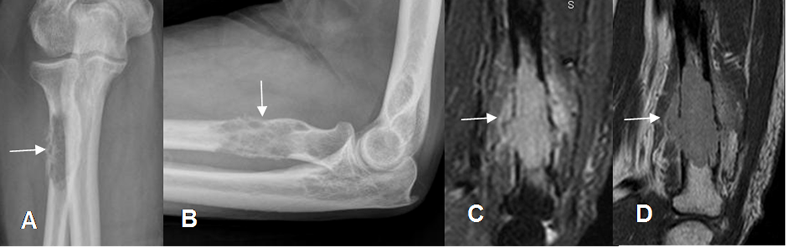

Fig 190. Mieloma.

A: Rx AP y B: Rx lateral. Lesión focal mixta en el tercio proximal del radio.

C: RM sagital en STIR y D: RM sagital en T1 con contraste. Lesión lítica, con ruptura de la cortical y masa de tejidos blandos que realza, por plasmocitoma solitario.